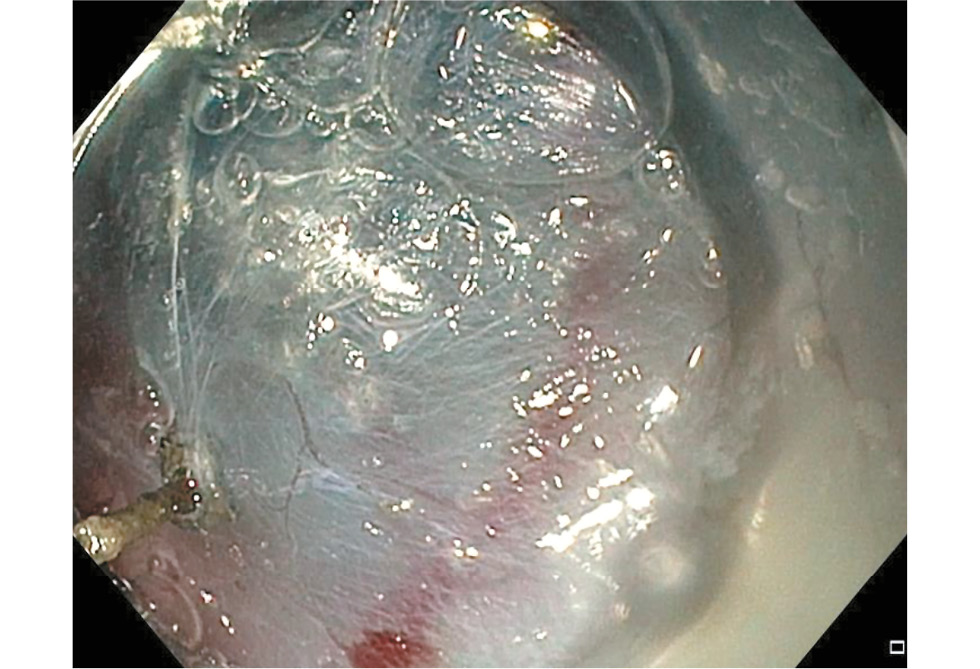

Методика ПОЭМ состояла из 3 этапов:

- Миотомия циркулярных волокон. Начиная на 2 см дистальнее нижней границы доступа в подслизистый слой пищевода поэтапно пересекали циркулярные мышечные волокна пищевода, нижнего пищеводного сфинктера и кардиального отдела желудка в режиме спрей-коагуляции. Миотомию распространяли на 2 см дистальнее пищеводно-желудочного перехода. После её завершения тщательно контролировали гемостаз и целостность слизистой оболочки пищевода, покрывающей данный тоннель (рис. 4).

Рис. 4. Пероральная эндоскопическая миотомия: выполнение миотомии.

Fig. 4. Peroral endoscopic myotomy: performing a myotomy.